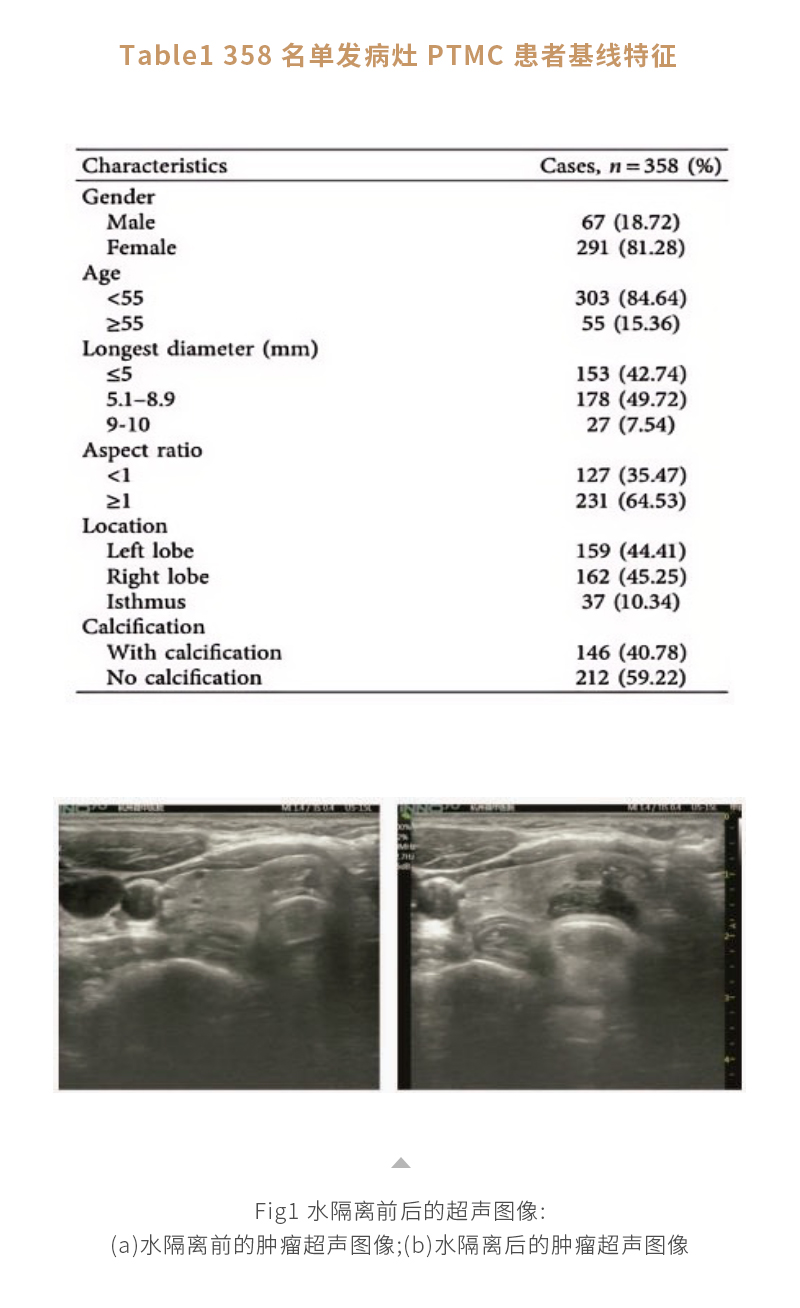

甲状腺癌热消融——【海杰亚科研资讯】第278期